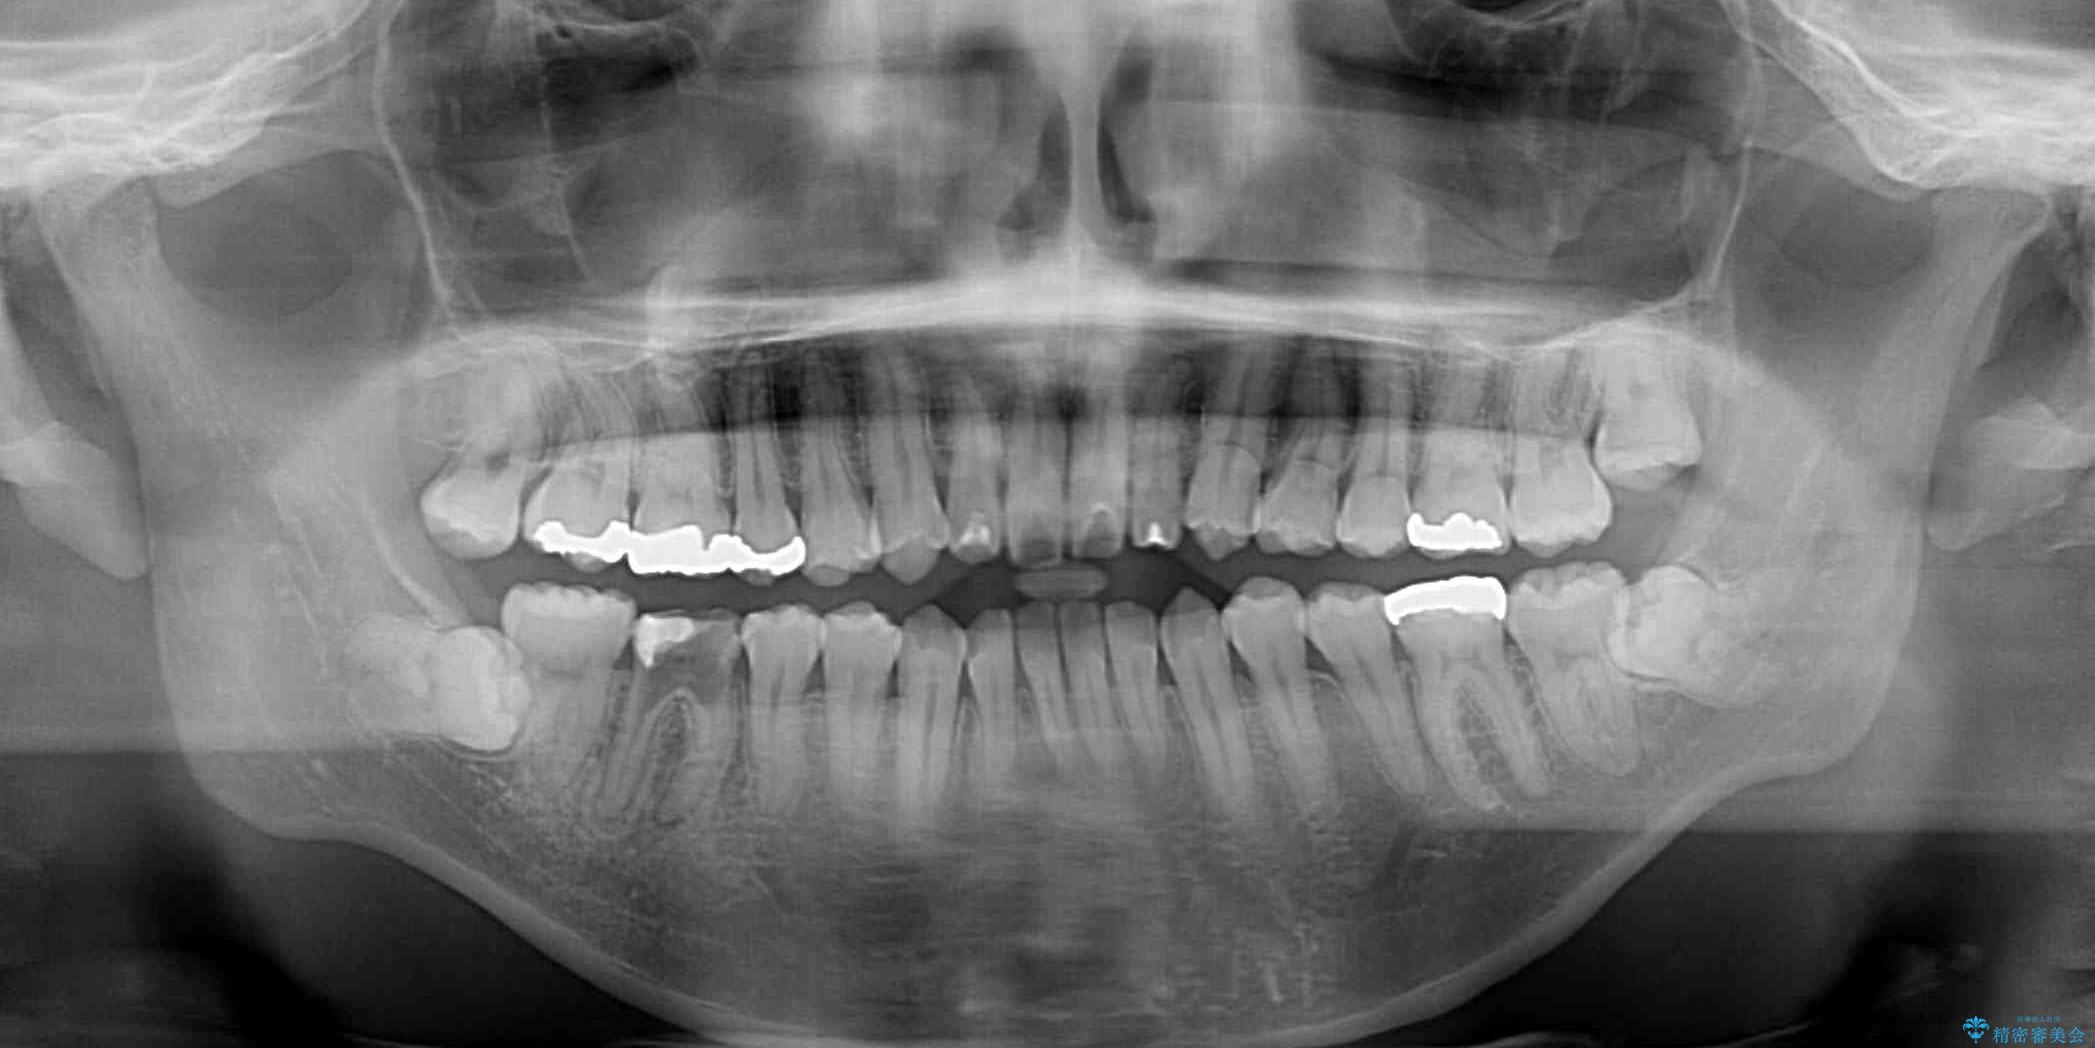

精密検査の結果、上下左右の小臼歯4本を抜歯し、そのスペースに前歯を後方へ移動させる矯正治療をご提案しました。

治療期間は約2年。

少しずつ前歯を後ろに下げていくことで、横顔のラインが整い、口元の“出っ張り感”が解消。

治療後には「自然に笑えるようになった」と嬉しいお声をいただきました。